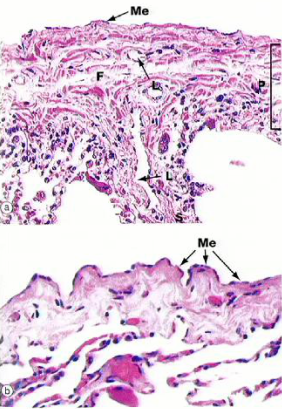

What cell type is pleura?